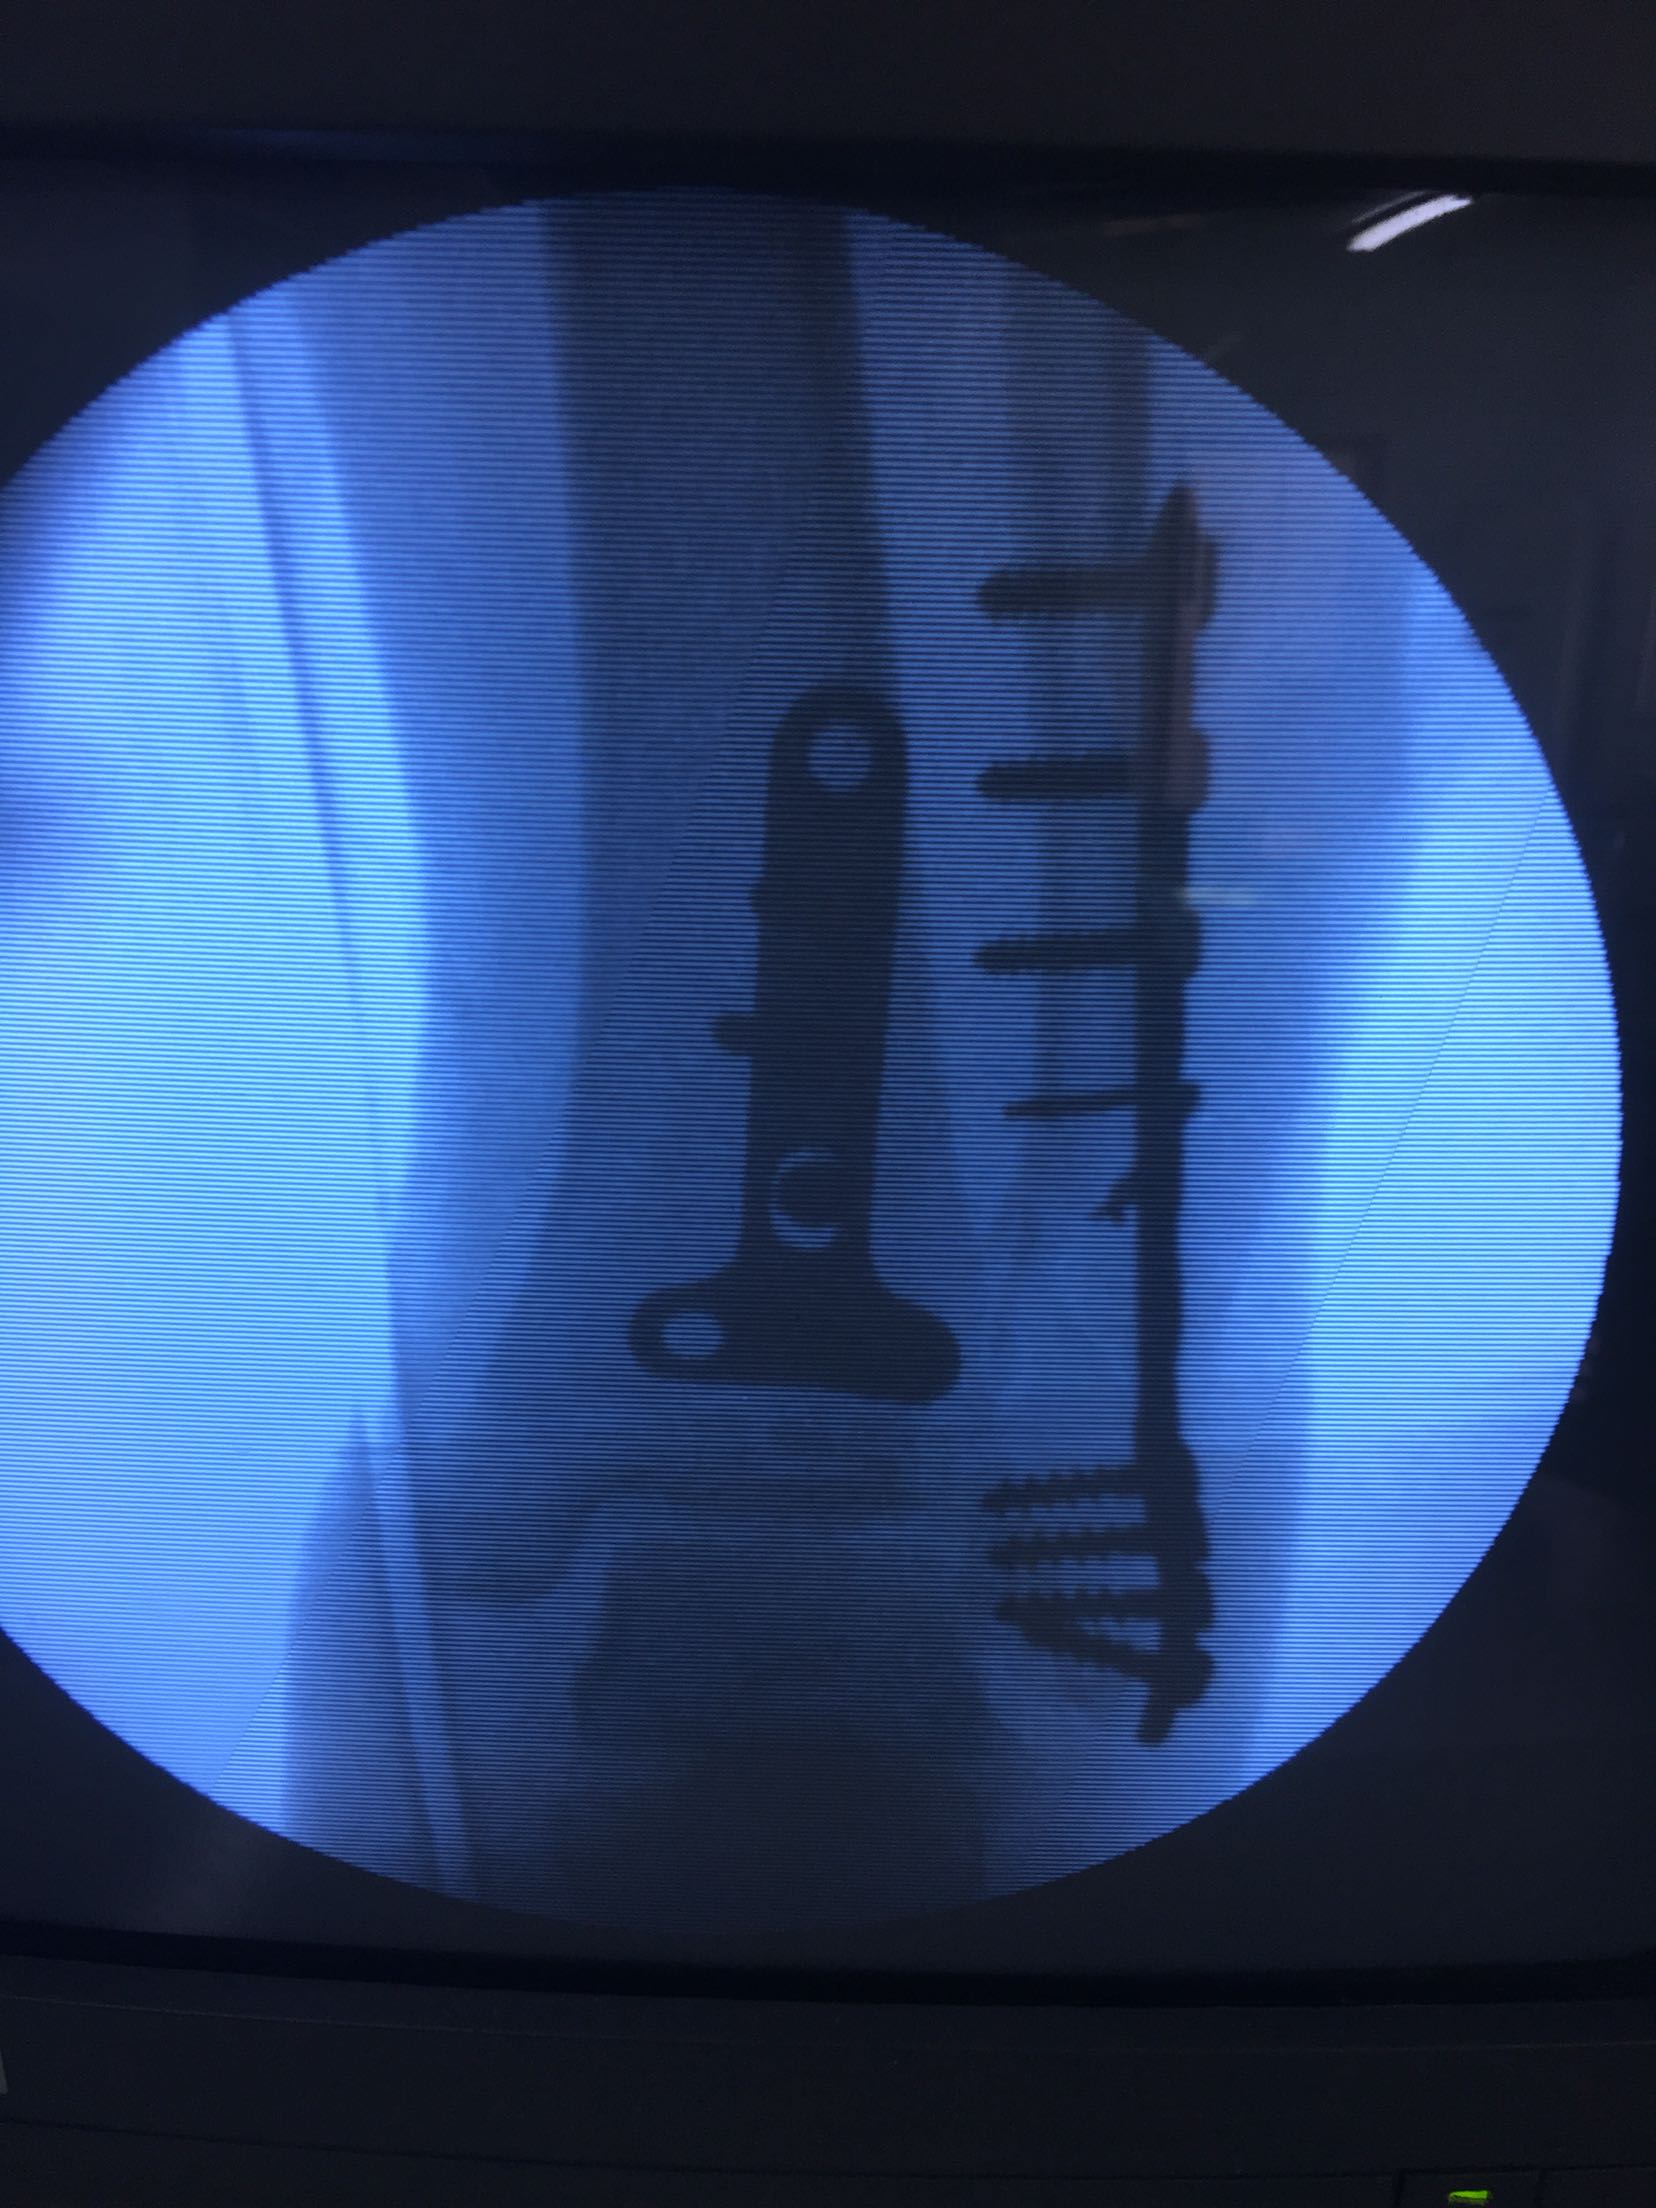

急诊在局麻行左跟骨结节骨牵引术一周。今日在腰麻下行切复内固定术,术后抗炎,消肿止痛等处理,石膏托制动3-4周。